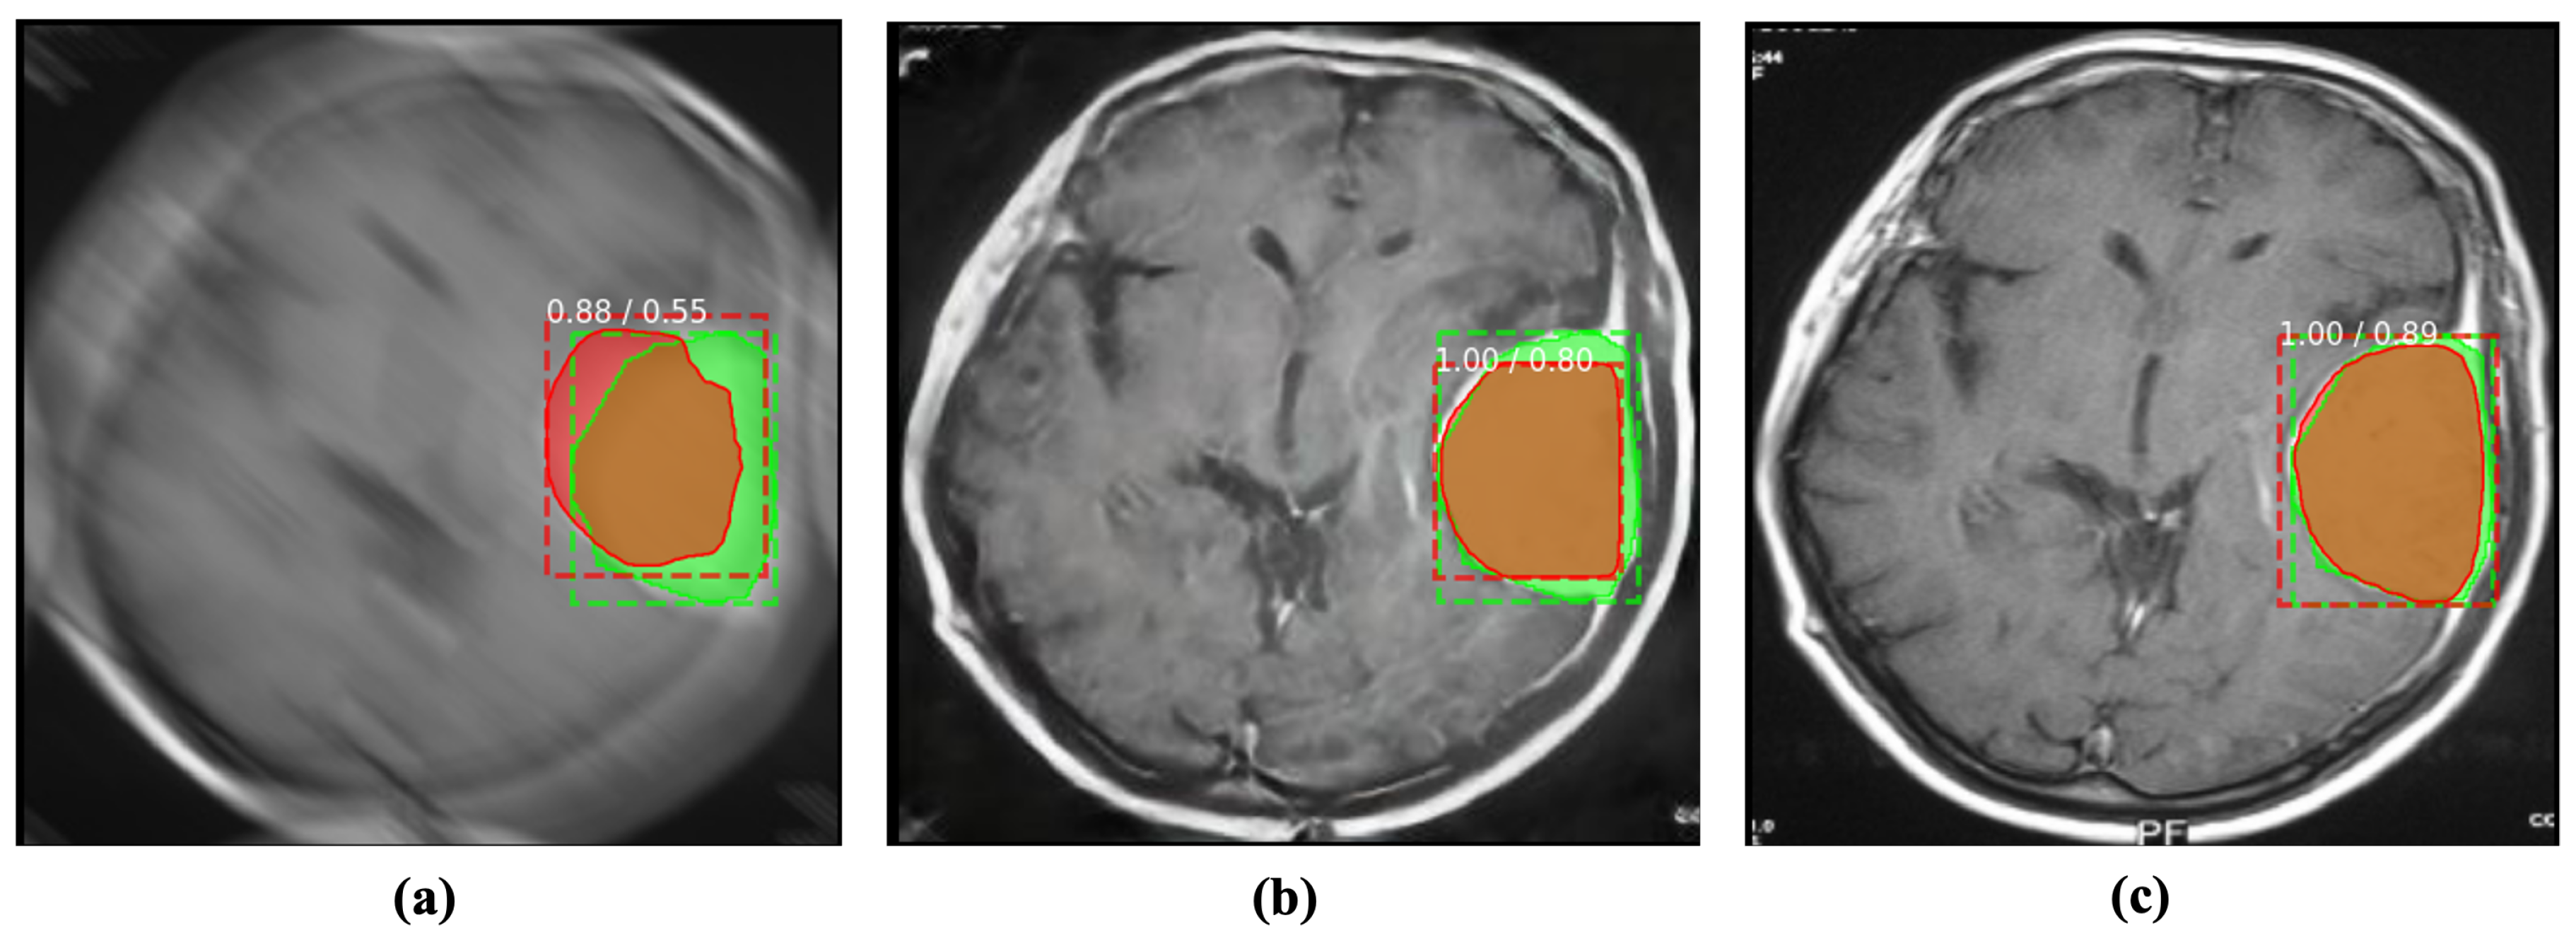

4.2.2. Detection

Similar to segmentation, abnormality detection is another widely used application in CAD. Such detection methods predict the region of abnormal issues or foreign bodies in a given medical image. Blind motion blurs can deteriorate the performance of such deep networks as well. We evaluated the performance of SOTA Mask R-CNN [37] with blurs in brain tumor detection. Despite being a well establish detection method, Mask R-CNN substantially suffers from blurs in the input image. Inversely, the proposed MID method can help the detection model by enhancing and removing blurs from the given input, as shown in Figure 7.

Figure 7.

Incorporating the proposed method for deblurring medical images can improve the performance of abnormality detection. The red and green regions represent the area segmented by the deep model and the actual (ground-truth) affected region. (a) Blurry image + Mask R-CNN [37]. (b) Deblurred obtained by proposed method + Mask R-CNN [37]. (c) Reference image + Mask R-CNN [37].